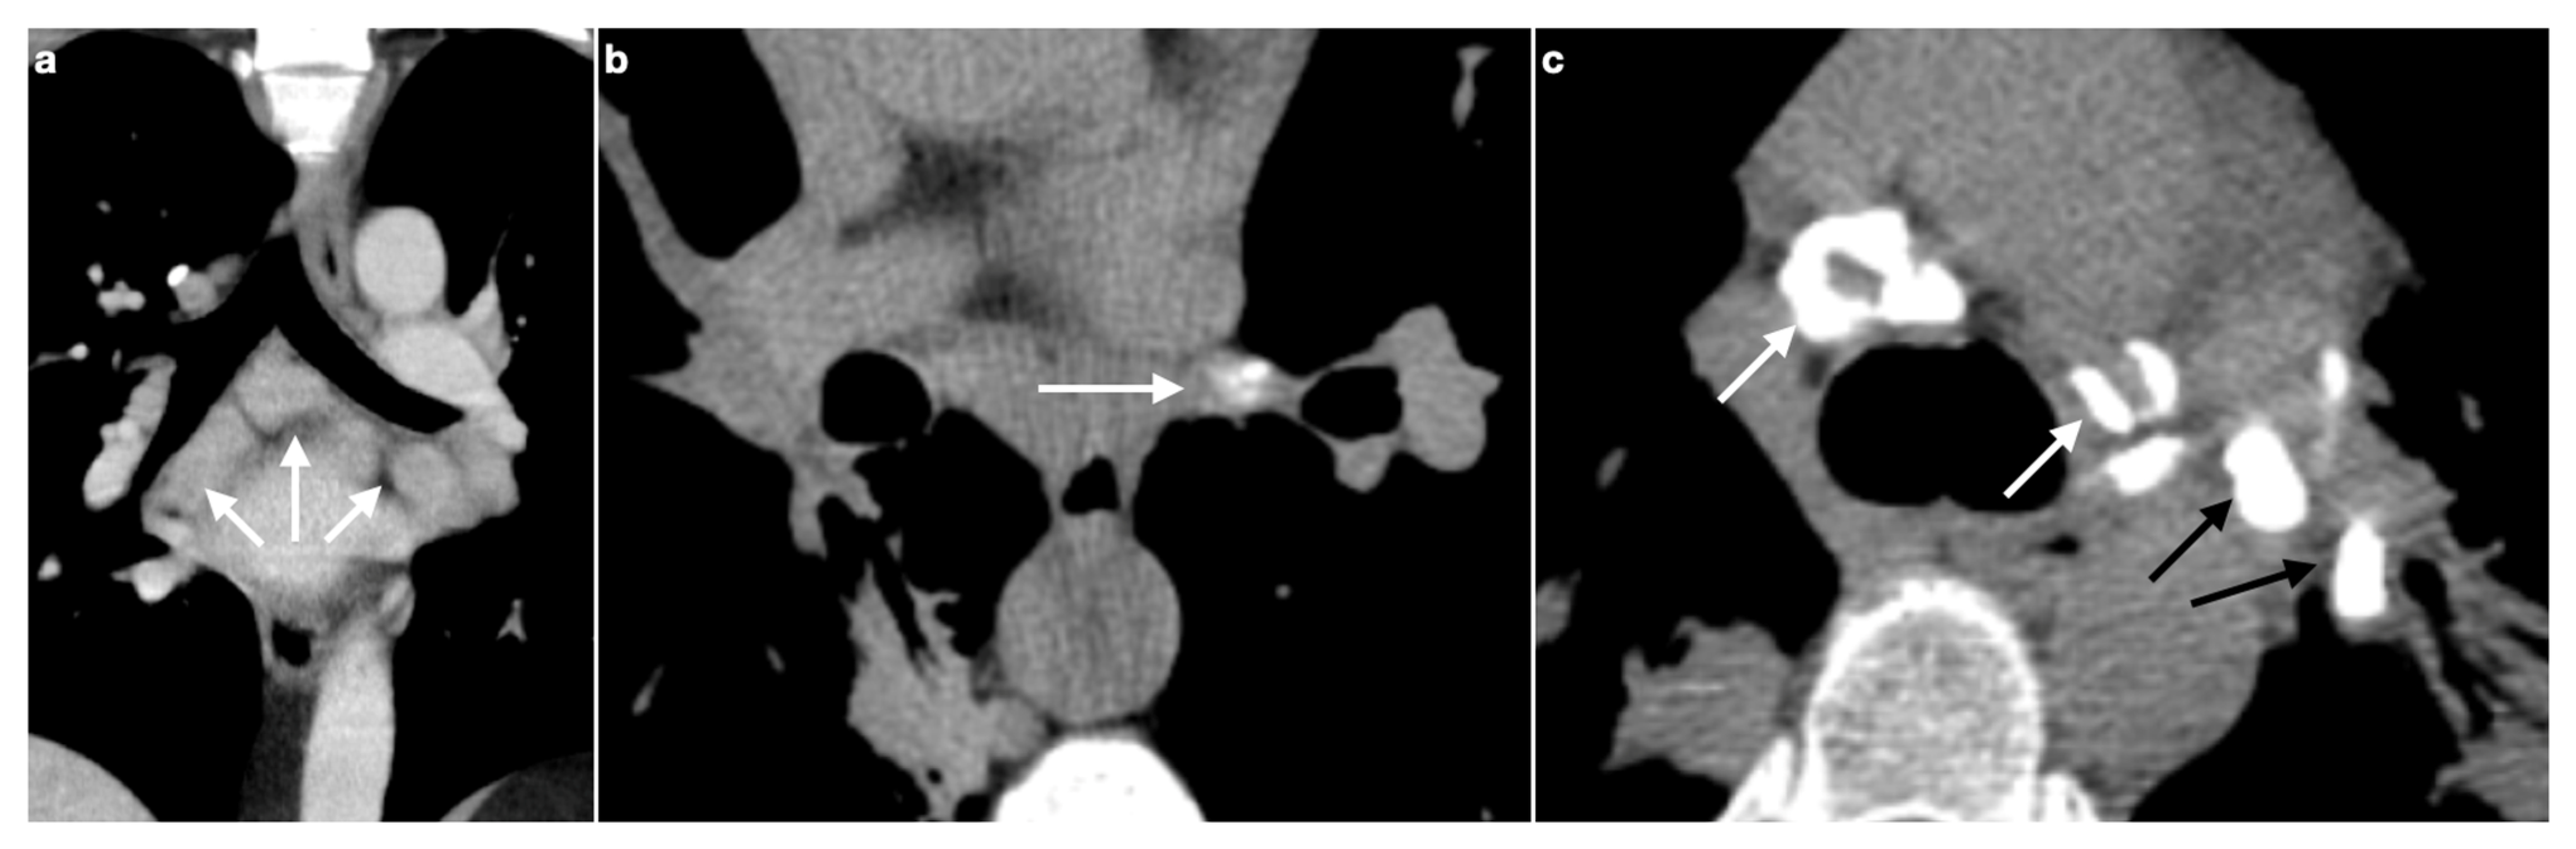

3. Lymphadenopathy

3.1. Typical Imaging

Calcifications

3.2. Atypical Imaging